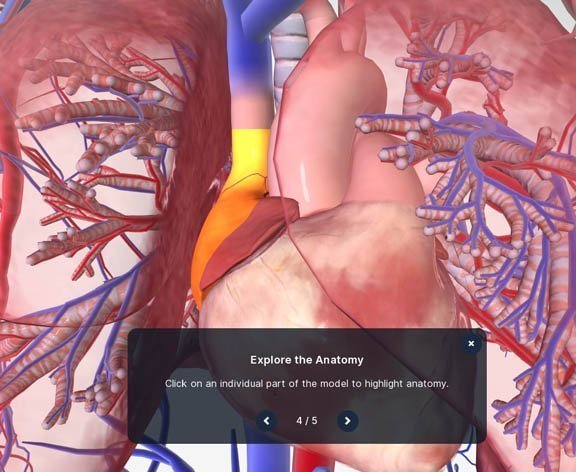

જુદા જુદા ભાગ ક્લિક કરીને માત્ર એ જ દેખાય એવું પણ કરી શકાશે. જેમ કે હૃદયના વિવિધ ભાગ પર ક્લિક કરી, તેના વિશે વધુ જાણી શકાશે. પીસીમાં દરેક ભાગ વિશે ઘણી વિસ્તૃત માહિતી મળશે.

જુદા જુદા ભાગ ક્લિક કરીને માત્ર એ જ દેખાય એવું પણ કરી શકાશે. જેમ કે હૃદયના વિવિધ ભાગ પર ક્લિક કરી, તેના વિશે વધુ જાણી શકાશે. પીસીમાં દરેક ભાગ વિશે ઘણી વિસ્તૃત માહિતી મળશે.